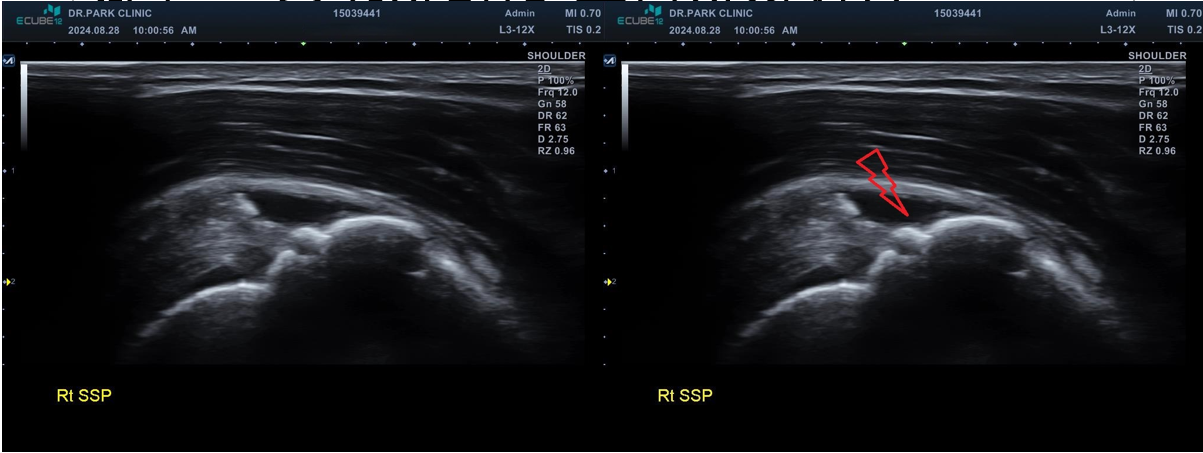

마지막 초음파에서는 어깨 극상근의 파열 소견이 관찰되고 있습니다. 정확한건 mri 를 찍어봐야 하겠지만 찢어진 길이와 정도로 봐서는 수술이 필요한 극상근 전층파열로 생각이 됩니다.

나 : 초음파상에서 어깨 극상근이라는 힘줄 파열이 관찰되네요. 이게 제일 문제입니다

나 : 수술 여부는 MRI를 찍어야만 정확히 결정되는 거지만.... 초음파에서 이정도 파열인 경우 보통 수술 하는게 좋습니다.